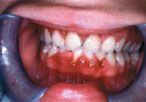

When considering the bacterial load, chronic inflammation and rapid levels of tissue turnover in periodontal tissues, it is not surprising that many systemic diseases present with oral and periodontal clinical changes. For example the impairment of host defenses in poorly controlled diabetic patients will result in markedly enlarged gingival tissues and bone loss. Similar patterns of increased bone loss can be seen in patients with Down’s Syndrome, diseases characterized by impairment of the host protective system such as neutropenia; leukemias (Fig. 1) and lymphomas; and a broad range of inherited and acquired diseases that result in impairment of one or more cells, proteins, etc., which are essential to combat infection.